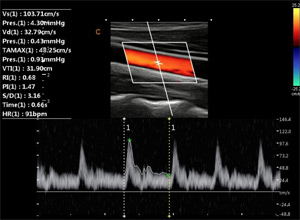

Сосудистый пакет:

- Автообсчет допплеровского спектра (в том числе в реальном времени)

Тканевой допплер

Цветной и спектральный тканевой допплер позволяет измерять деформации и скорости деформаций сердечной стенки

Автотрассировка спектра

Автоматическое оконтуривание допплеровского спектра с быстрым расчётом всех необходимых параметров гемодинамики: PI пульсационный индекс, RI индекс резистентности, ЧСС, S/D, систолическая и диастолическая скорости, TAMAX средняя скорость, градиент давления, VTI интегральная скорость, время цикла.